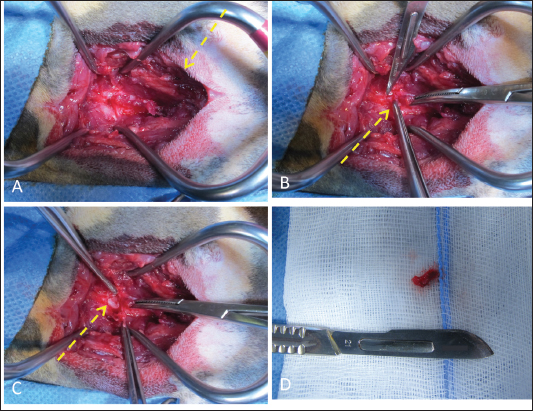

Fig. 4. Surgical approach to vertebral fracture of C4 through a dorsal cervical approach. (A) Once the surgical access was performed, the epaxial muscles showed gross evidence of blunt trauma (yellow dotted arrow). (B) The fourth and fifth cervical vertebrae were skeletonized to evidence the bone fracture. Then, the caudal fragment was grabbed, elevated, and removed, cutting the flavum ligament (note the bone fragment between the forceps, yellow dotted arrow). (C) The uncompressed spinal cord was visualized after the bone fragment was removed (yellow dotted arrow).

The cat was placed in sternal recumbency with the neck gently flexed in a neutral position. The skin was aseptically prepared, and a midline skin incision was made from the atlas to the level of the seventh cervical vertebra to explore the cervical region. The epaxial muscles showed evidence of blunt trauma without signs of direct laceration (Fig. 4A). The nuchal ligament was split longitudinally, and the cervical vertebrae spinous processes were identified. The multifidus muscle was elevated from the spinous processes to expose the dorsal lamina and perform the fourth and fifth cervical vertebrae skeletonization. The bone fracture was then identified at the dorsal lamina’s caudal margin of C4, caudal to the spinous process. The caudal fragment was grasped and elevated with bone forceps (Fig. 4B). The periosteum and ligamentum flavum lateral and caudal to the fragment were then severed and gently removed with a scalpel blade. The spinal cord below the fragment showed no gross alteration or signs of contusion (Fig. 4C). After removing the bone fragment, both fentanyl and ketamine CRIs were gradually tapered, and the cat remained normotensive with a normal heart rate until the end of the surgery. Once the surgical field was irrigated and adequate hemostasis was confirmed, the fascia, subcutaneous tissue, and skin were sutured in a routine fashion.